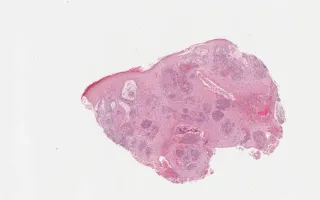

Biopsy of ulcerated leg lesion; also has a history of pneumonia, unresponsive to antibiotics.

Blastomyces dermatitidis is a fungal organism which can cause pneumonia and skin infections. The H&E image (this slide) shows epidermal/superficial dermal microabscesses with neutrophils as well as broad based, thick walled blastomyces organisms. The GMS silver stain (see Related Content) highlights the organisms (in black).

Blastomyces are found in the soil in the Ohio River and Mississippi River deltas, and the Great Lakes-St. Lawrence region. It commonly presents as pneumonia or as a skin infection. The cutaneous presentation often results in verrucous/papillary or ulcerative lesions. Histologically, blastomyces spores are typically 8-15 microns in size and exhibit broad-based budding. They can often be found in dermal microabscesses. The differential diagnosis would include other infections, including other fungi, but blastmycosis can mimic malignancy such as squamous cell carcinoma due to the presence of squamous hyperplasia.